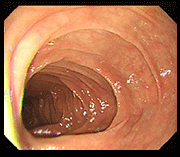

潰瘍性大腸炎前後の粘膜回復

腸粘膜のひどい炎症、発赤、潰瘍が治まり、滑らかで健康な状態に回復した事例です。

事例 1

治療前 治療前 腸内粘膜写真

治療後 治療後 腸内粘膜回復写真